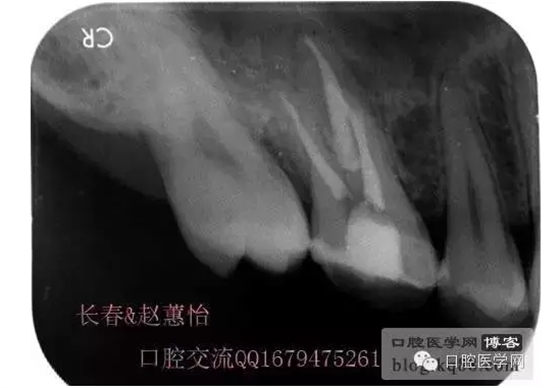

術(shù)后,明顯可見近中頰側(cè)根管臺(tái)階位置

越過臺(tái)階后小心預(yù)備直至大錐度銼可以順利進(jìn)術(shù)前片的小彎沒當(dāng)回事,哎